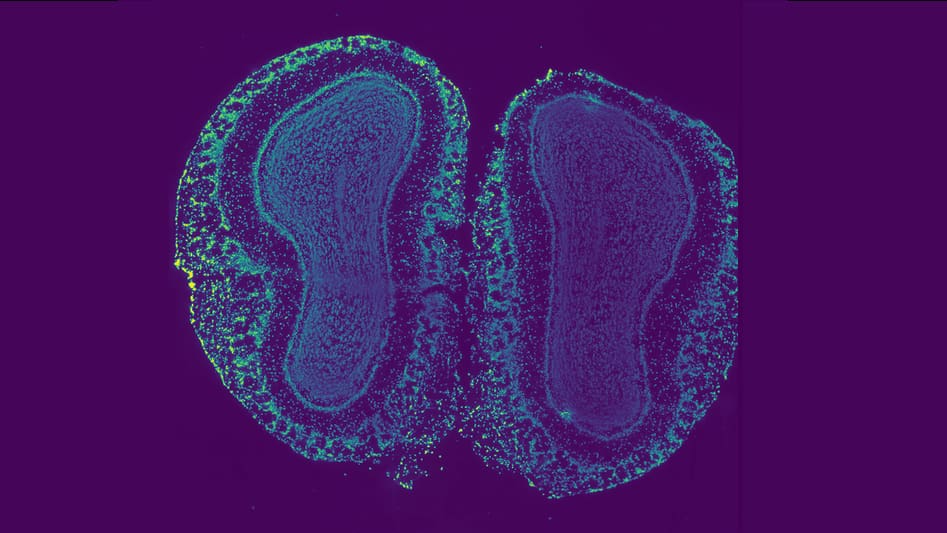

New algorithm reveals the hidden geometry of tissues